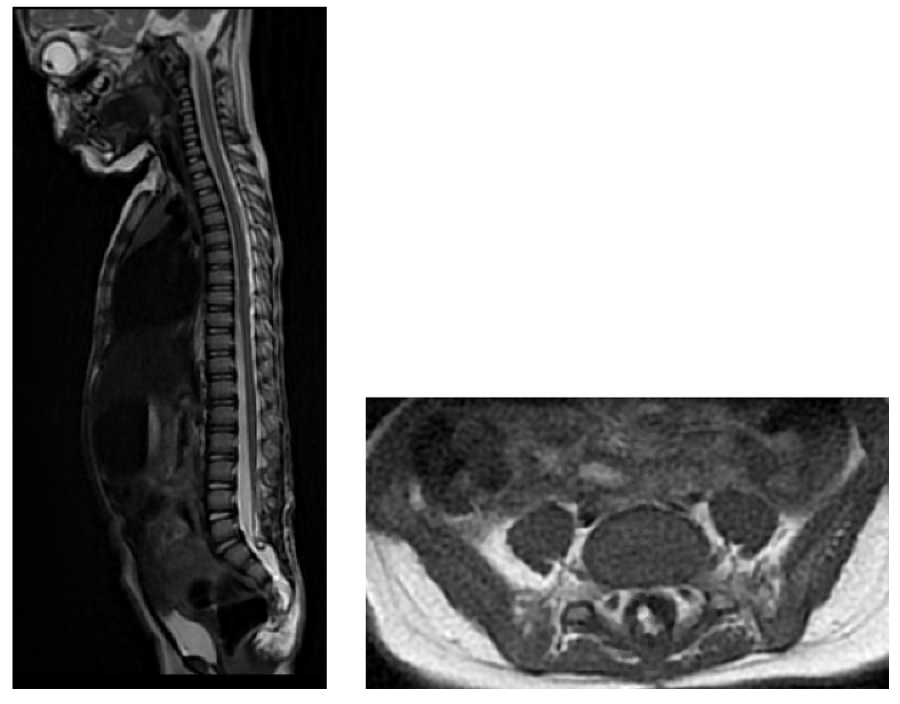

MRI 4 months post-surgery showed regression of the large syringomyelic cavity and signal abnormalities (figure 2). Bladder and renal ultrasound ordered at the same time was also normal. She was potty trained by 2 years and 3 months old. The last clinical follow-up was made earlier this year, she is now almost 4 years old and remains completely asymptomatic.

Figure 2: MRI findings at subacute worsening showing an extensive syringomyelia A: sagittal T2 B: sagittal T2 CISS) View Figure 2

Figure 3: MRI findings at 4-month post op follow up with complete clinical recovery A: sagittal T2showing complete regression of syringomyelia and restoration of perimedullary intradural CSF space, B: Axial T1 showing the lipomatous remainder at termination of spinal cord View Figure 3